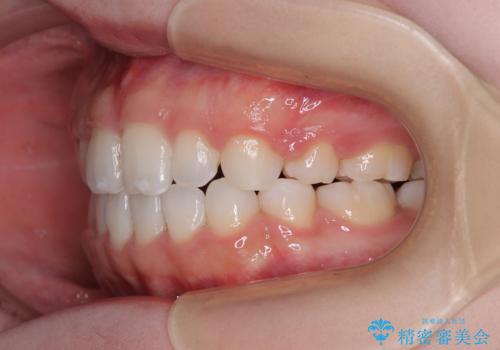

- メタルブラケット

- 1年9ヶ月

舌の突出癖により上下前歯は接触できず、更には前方に押し出されて出っ歯になっている状態でした。

上下左右の第一小臼歯4本を抜歯し、ワイヤー装置での抜歯矯正を行っていくのですが、原因である舌の突出癖を改善しないことには治療がうまく進められないため、舌のトレーニングを徹底するよう指導していくこととしました。

当初は舌のトレーニングをしっかりと行ってくださったおかげで、短い期間で治療を終えることができました。